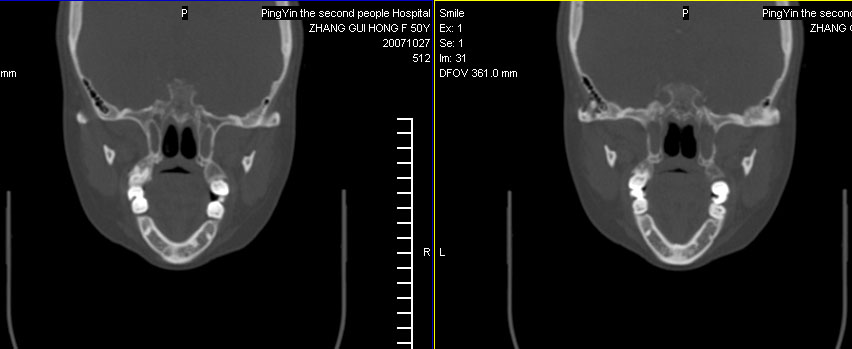

标题: CT10219:蝶鞍区有无异常?

女。50岁.头疼恶心半月余.双上颌窦区压疼明显,曾有高血压.现基本控制.

有问题,双侧侧脑室扩大,感觉鞍区有肿块,建议增强扫描.

感觉鞍区异常,建议增强扫描.

感觉鞍区异常,建议增强扫描或mri!